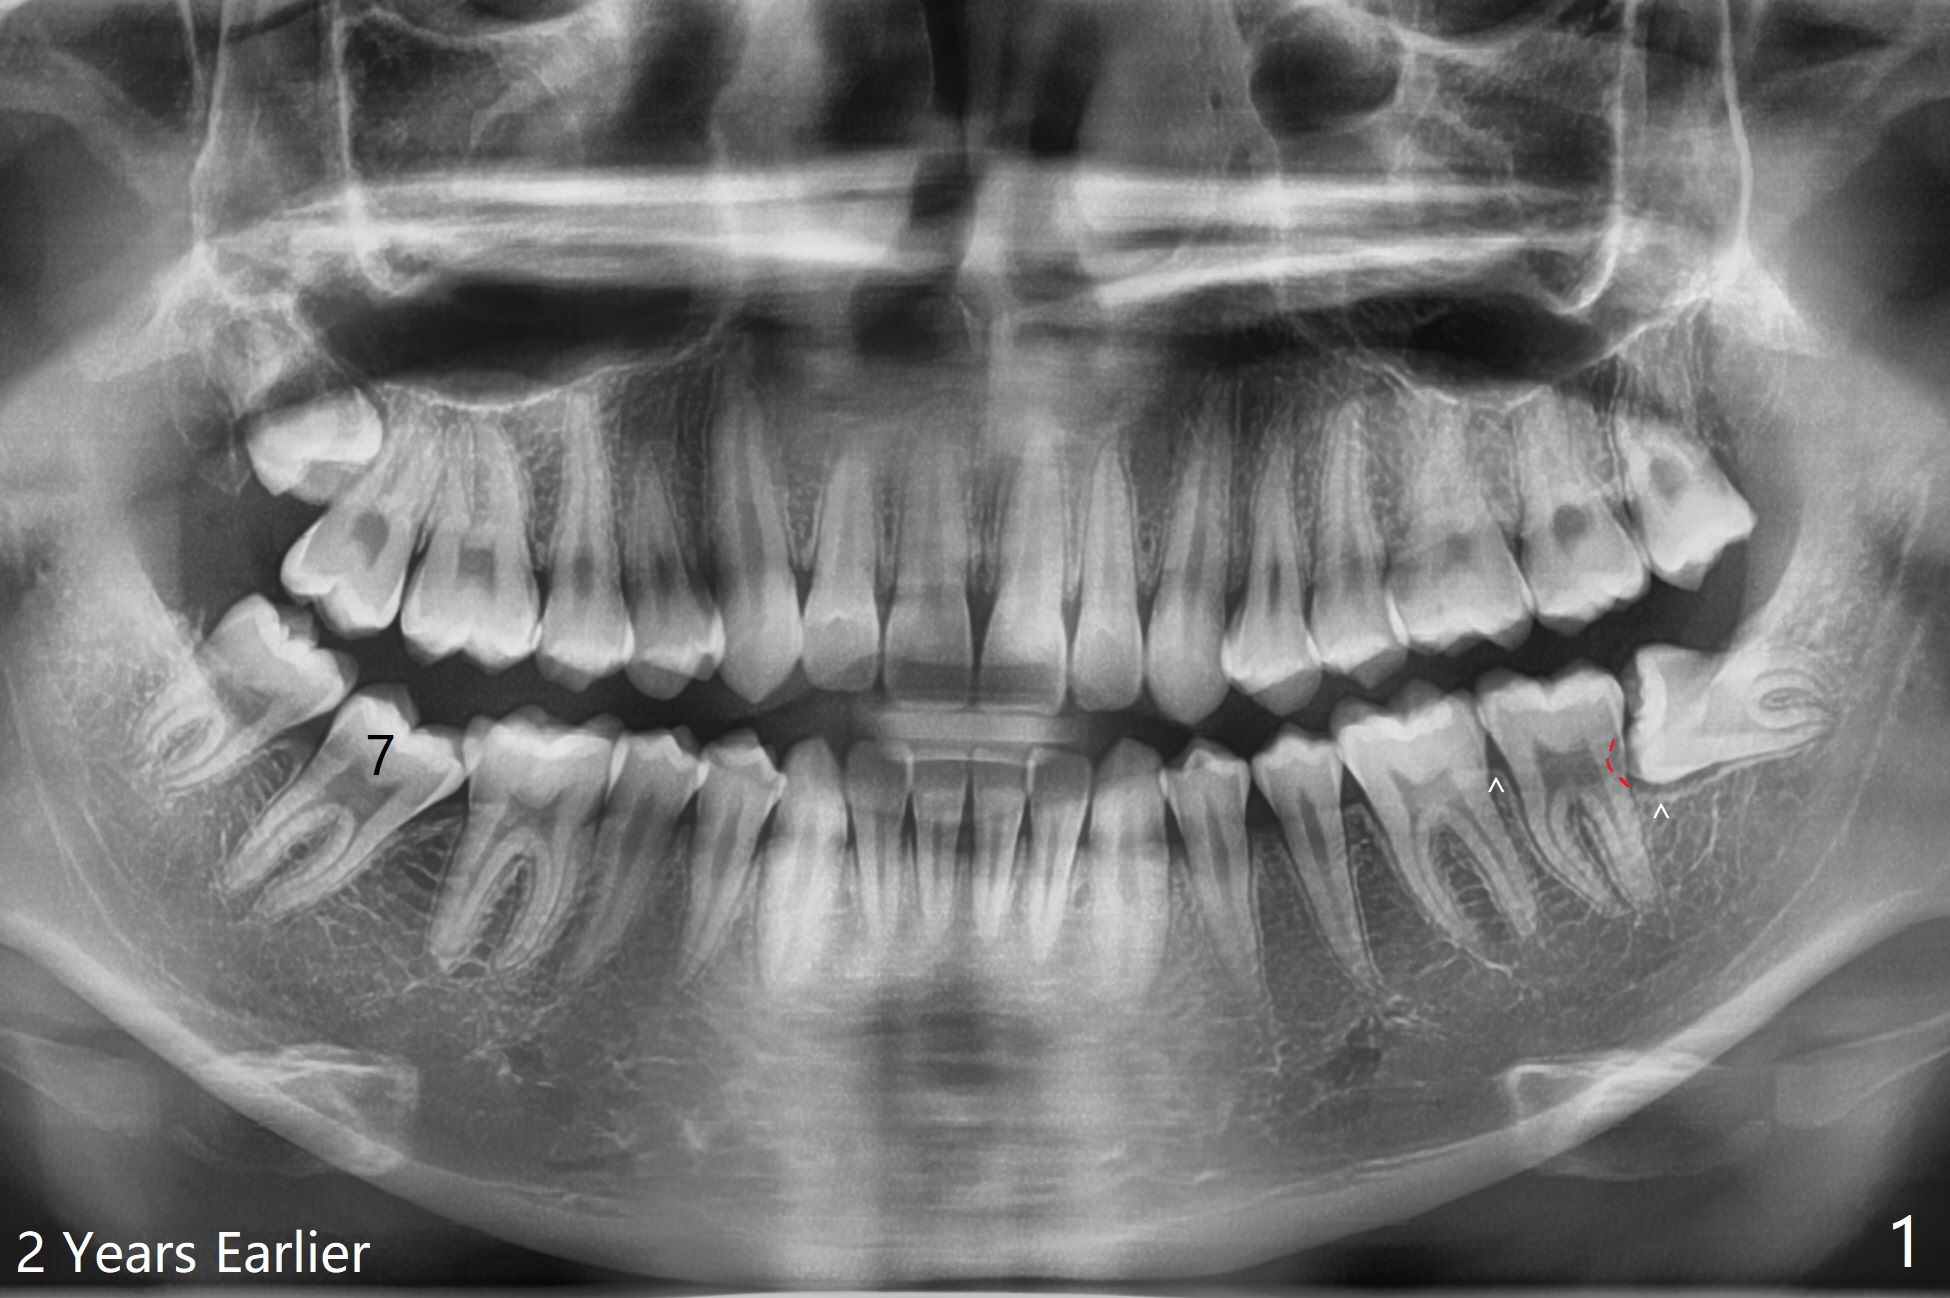

提高下第二磨牙远中骨质

20岁男两年前来诊所会诊智齿拔除(图一),洗牙后不见踪影,昨天回来要求拔除左下智齿,口腔卫生仍不佳。其实智齿位于第二磨牙远中颊侧(图一:红虚线),而且远中牙槽嵴低于近中(箭头)。所以拔牙(多次切割)后,半块胶原塞根尖(图二:C),而粘性骨粉(S)放置于牙槽窝牙冠,即第二磨牙远中,之上又放置半块胶原塞和两块PRF膜,促使伤口愈合,防止干槽症,PGA缝线。